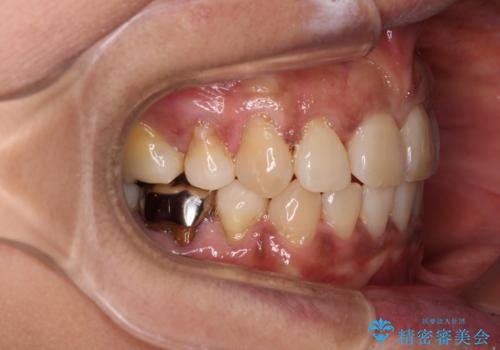

- 八重歯やクロスバイトを気にして来院された患者様です。

口元の突出感はありませんでしたが、デコボコが強く、非抜歯矯正とすると出っ歯仕上がりとなる可能性があったため、上下左右の第一小臼歯4本を抜歯し、ワイヤー装置にて矯正治療を行うこととしました。

抜歯矯正により口元が引っ込みすぎて、ほうれい線が顕著となるのではないかと心配しておりましたが、矯正後にほうれい線が気になることはなく、口元もすっきりとした感じになりました。